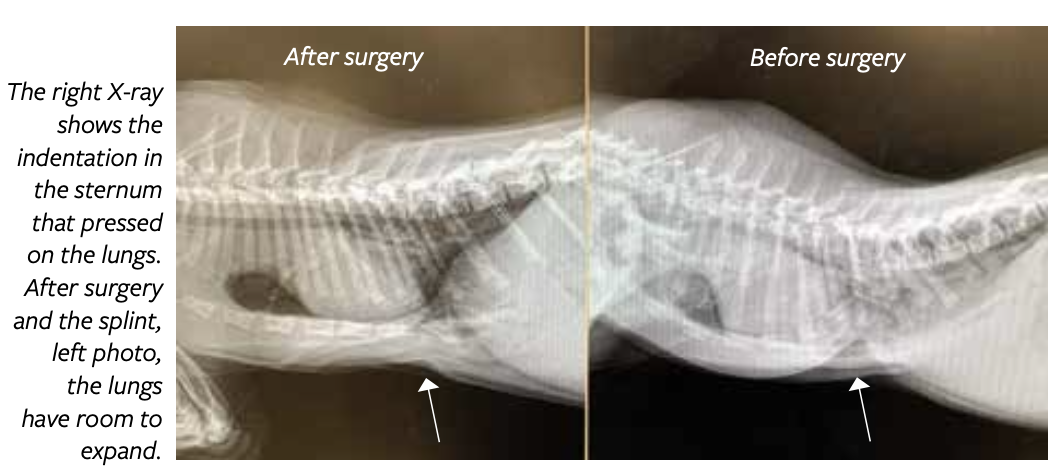

“Pectus excavatum is a relatively uncommon condition of young kittens in which a large indentation of the sternum, or breastbone, develops,” says Daniel Lopez, DVM, DACVS, assistant professor of small animal surgery at Cornell University’s College of Veterinary Medicine.

With PE, the sternum (lower part of the rib cage) is malformed, pushing up into the thorax and creating a space that more closely resembles a rectangle.

PE can be mild, moderate, or severe. Mild cases may have enough room in the thoracic cavity for their lungs to expand almost normally and have no problem living with the deformity. Moderate and severe cases will likely have clinical signs. X-rays help define the nature and severity of the defect, which helps guide decision making regarding treatment.

Treatment for severe cases of PE is surgical. The kitten is placed under general anesthesia and cast material is used to create a splint for the underside of the chest. Sutures are placed around the bones of the sternum in the affected area, pulled through the external splint, and tightened. This pulls the inwardly deviated sternum back out to a more normal position, effectively creating more space within the thorax for the lungs to expand.

The veterinary surgical team at Cornell University’s College of Veterinary Medicine applied a mesh splint to Cotton after surgery to pull the inwardly deviated sternum back to a normal space to allow for the lungs to expand. Once healed, the splint was removed.